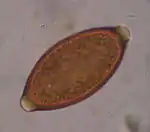

Trichuris trichiura

Trichuris trichiura, ou Trichocephalus trichiuris, est une espèce de nématodes (les nématodes sont un embranchement de vers non segmentés, recouverts d'une épaisse cuticule et menant une vie libre ou parasitaire). C'est l'un des parasites du tube digestif humain, dont des œufs fossilisés sont encore trouvés sur des lieux de fouilles archéologiques préhistoriques[1].

Description

C’est un nématode de 3 à 5 cm de long.